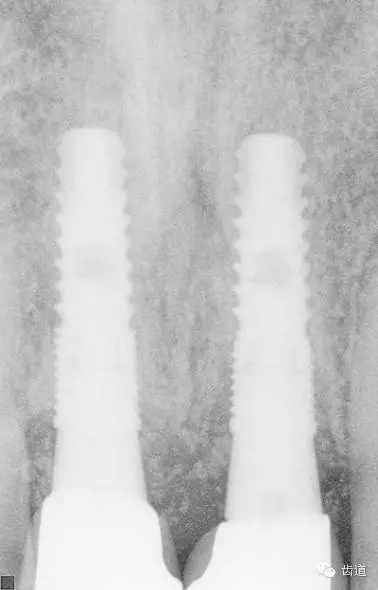

術(shù)后CT

戴牙后CT

本病例為前牙外傷致根折,牙周無(wú)明顯炎癥,唇側(cè)骨板厚度大于1mm且根方骨量充足,適合即刻種植。術(shù)前簡(jiǎn)易導(dǎo)板的制作以及術(shù)中牙周探針精確的測(cè)量,保證了種植體的三維位置及軸向均按標(biāo)準(zhǔn)的即刻種植手術(shù)進(jìn)行。術(shù)后參考拔除牙齒的頸部形態(tài)制作個(gè)性化愈合基臺(tái),實(shí)現(xiàn)了對(duì)牙齦塑型的早期干預(yù),打破了傳統(tǒng)二期牙齦成型的做法,所成型的牙齦袖口與之前的天然牙相似,有利于維持牙齦形態(tài)的穩(wěn)定和美觀。